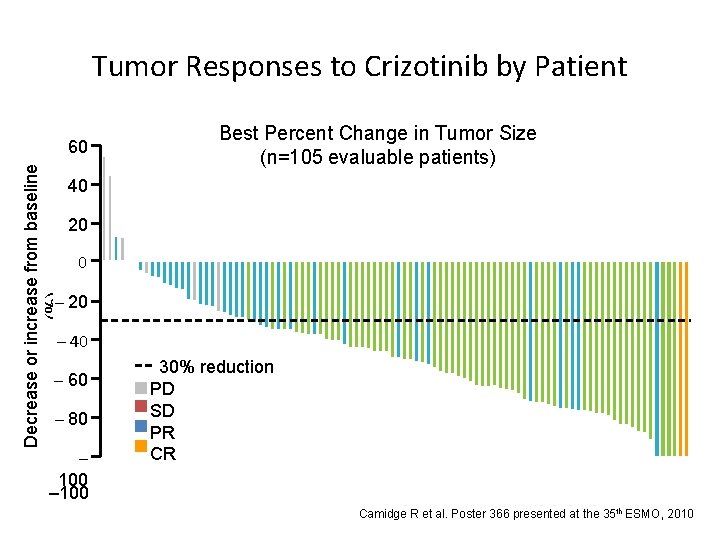

Decrease or increase from baseline (%) Tumor Responses to Crizotinib by Patient 60 50 40 Best Percent Change in Tumor Size (n=105 evaluable patients) 20 20 0 –– 10 20 – 40 – 60 –– 70 80 – 100 30% reduction PD SD PR CR Camidge R et al. Poster 366 presented at the 35 th ESMO, 2010